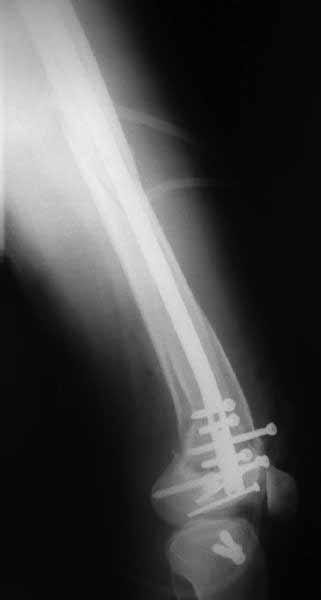

Ответ на эту часть Вашего поста – вложенный файл. Больная оперирована неделю назад по поводу открытого перелома дистального эпиметафиза бедренной кости. После операции она идёт в рентгенкабинет для выполнения послеоперационной контрольной рентгенографии, представленной на слайдах 10 и 11. Узнав, почему её фотографируют, просила передать Вам, Антон, привет.

В приложении пример недавней операции, C3, открытая репозиция, фиксация мыщелков спицами и винтами, ретроградный синтез большеберцовым гвоздем 10,5 мм диаметром, винты 5 мм.